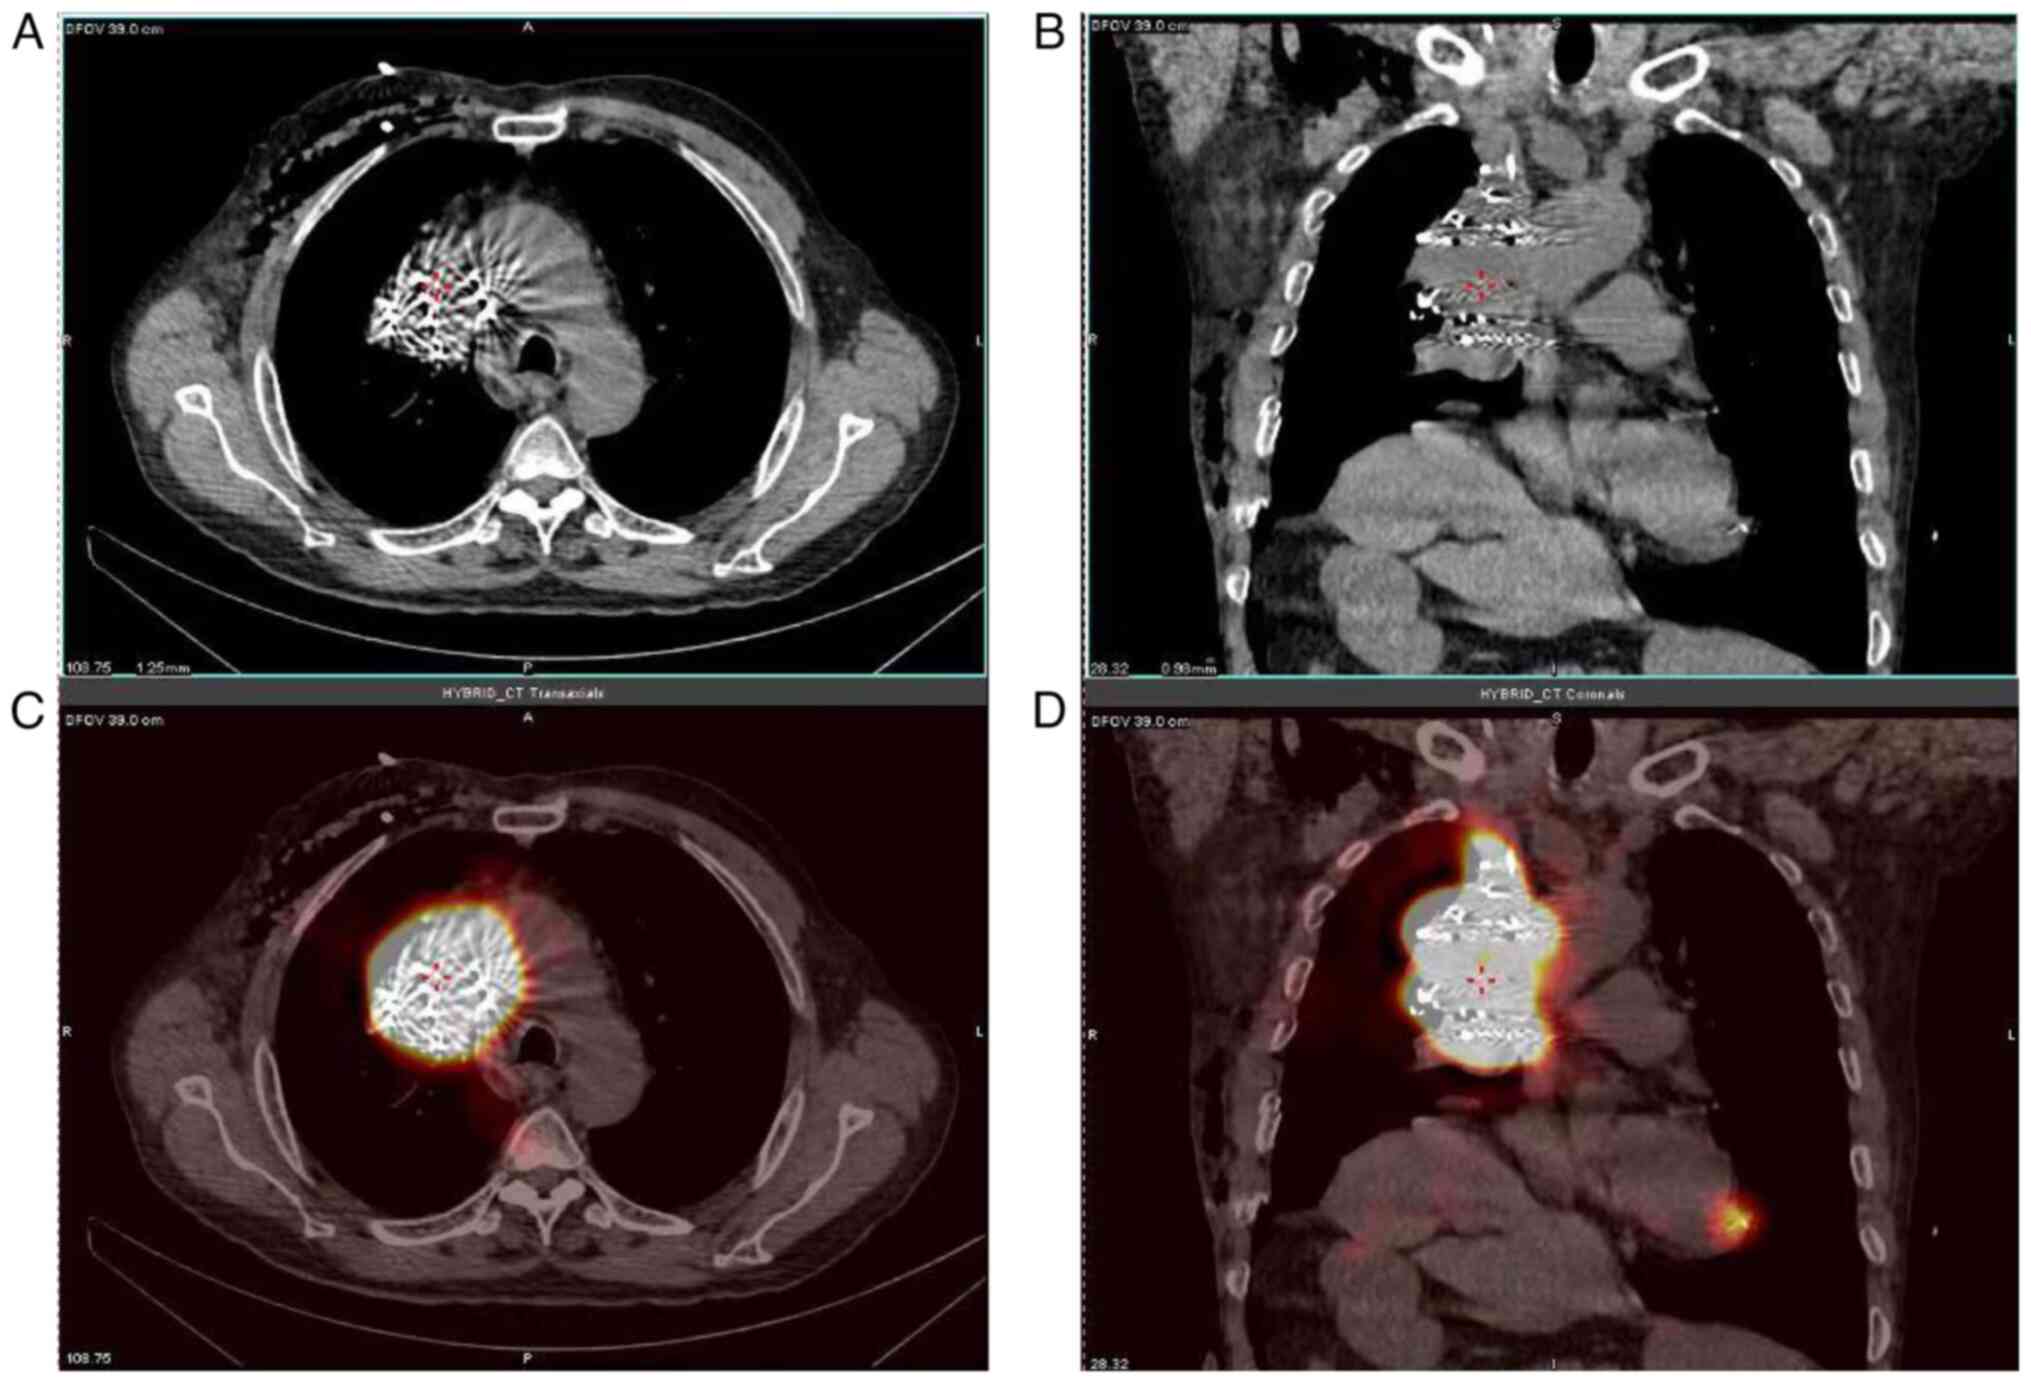

Before each treatment, the informed consent of the patient was obtained, and the treatments were performed with Hebei General Hospital institutional approval. Prior to I125 seed implantation, the patient was immobilized using a vacuum cushion (size: 120×80×4 cm3; Medical Device Network). A line was drawn using a CT laser on the tumor projection surface of the skin, and three marks were posted 3–4 cm away from each other on this positioning line. A CT scan was obtained (slice thickness, 5 mm; data not shown). A treatment plan was designed using the TPS (Panther Brachy v5.0 TPS; Prowess Inc.) to determine the dose, number and location of the I125 seeds to be implanted. The target volume was carefully determined according to the CT findings. Clinical target volume was considered as the gross target volume with a 5-mm boundary around it, and it was restricted by the volume of critical organs. DVH parameters were recommended for the evaluation of target volume and organs at risk. The dose distribution to target volume and organs at risk are shown in Fig. 1. The edge of the clinical target volume was covered by an isodose line of 90% of the prescribed dose and the prescribed dose of the seed strands. The day before the procedure, the 3D-printed template was sterilized (Fig. 2). After the procedure, single-photon emission CT was performed to ensure that the I125 seeds had been implanted in the correct locations based on the template (Fig. 3).

Figure 3.

Postoperative SPECT particles cover the target area. (A) is the CT image (B) is the axial CT image immediately after particle implantation; (C) is relative SPECT showed that the radioactive concentration of particles basically covered the target area. (D) is the axial SPECT. SPECT, single photon emission computed tomography.